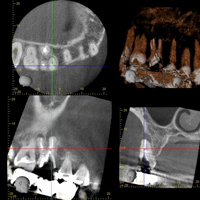

• 検査・診断

レントゲン

問診・視診・触診・打診・レントゲン検査(単純X線撮影、CT)・歯周ポケット検査などにより、歯を詳しく検査します。病気の原因を診断した上で治療方法を決定します。